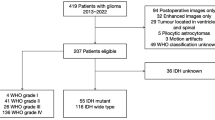

All study patients were initially diagnosed with glioma, 141 from the Cancer Genome Atlas and 131 from our tertiary institution, as training and validation sets, respectively. Images were analyzed by three neuroradiologists with 1–7 years of experience. MRI features including contrast enhancement pattern, necrosis, margin, edema, T2/FLAIR mismatch, internal cyst, and cerebral blood volume higher than normal cortex were reported using a structured reporting system. The pathology was stratified into five risk types: (1) oligodendroglioma, isocitrate dehydrogenase [IDH]-mutant, 1p19q co-deleted; (2) diffuse astrocytoma, IDH-mutant, grade II–III; (3) glioblastoma, IDH-mutant, grade IV; (4) diffuse astrocytoma, IDH-wild, grade II–III; and (5) glioblastoma, IDH-wild, grade IV. Significant predictors were selected using multivariate logistic regression, and diagnostic performance was tested using a validation set.

Results